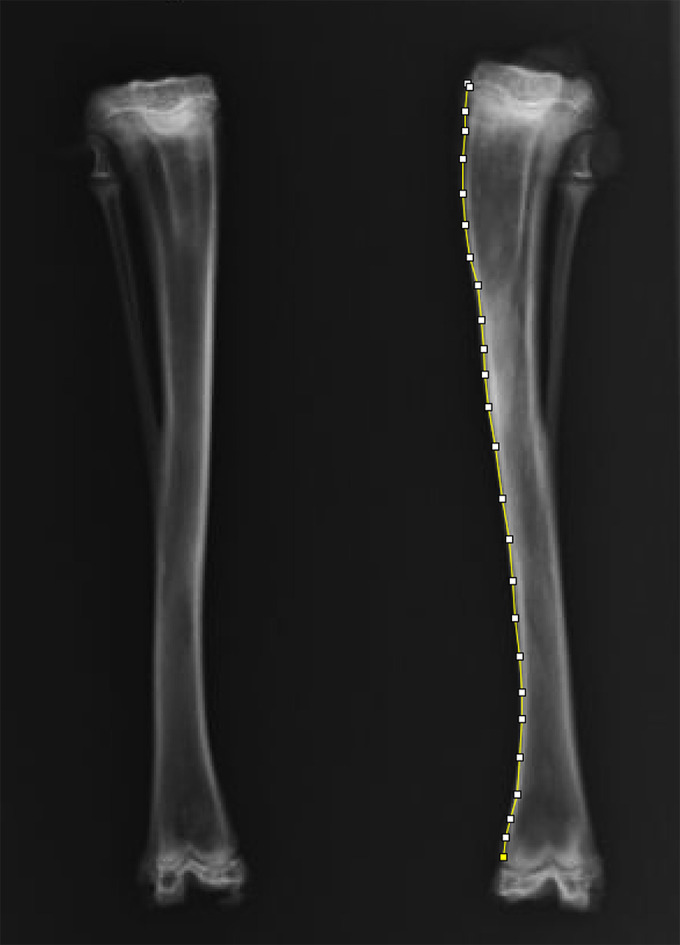

Methods: In Experiment 1, 38 skeletally immature male New Zealand white rabbits were randomized into one of four groups: a metaphyseal hole created at 5, 10, or 15 mm distal to the physis of the left proximal tibia with the hole filled with bone wax, or a sham control group. In Experiment 2, after establishing the distance associated with the most overgrowth, a defect was created at 10 mm distal to the physis in 20 additional rabbits, which were randomly assigned to have the defect filled with Tisseel, or be left unfilled. The rabbits were euthanized six weeks postoperatively.

Results: The length and rate of overgrowth were higher in the groups with holes drilled 5 and 10 mm distal to the physis compared to the sham group. A significant increase in new bone width was observed in the 10 mm distal hole group. Growth stimulation in both radiological and histological analyses was not significant in the unfilled and Tisseel groups. Valgus deformities were observed in all groups with metaphyseal holes compared to the sham group.